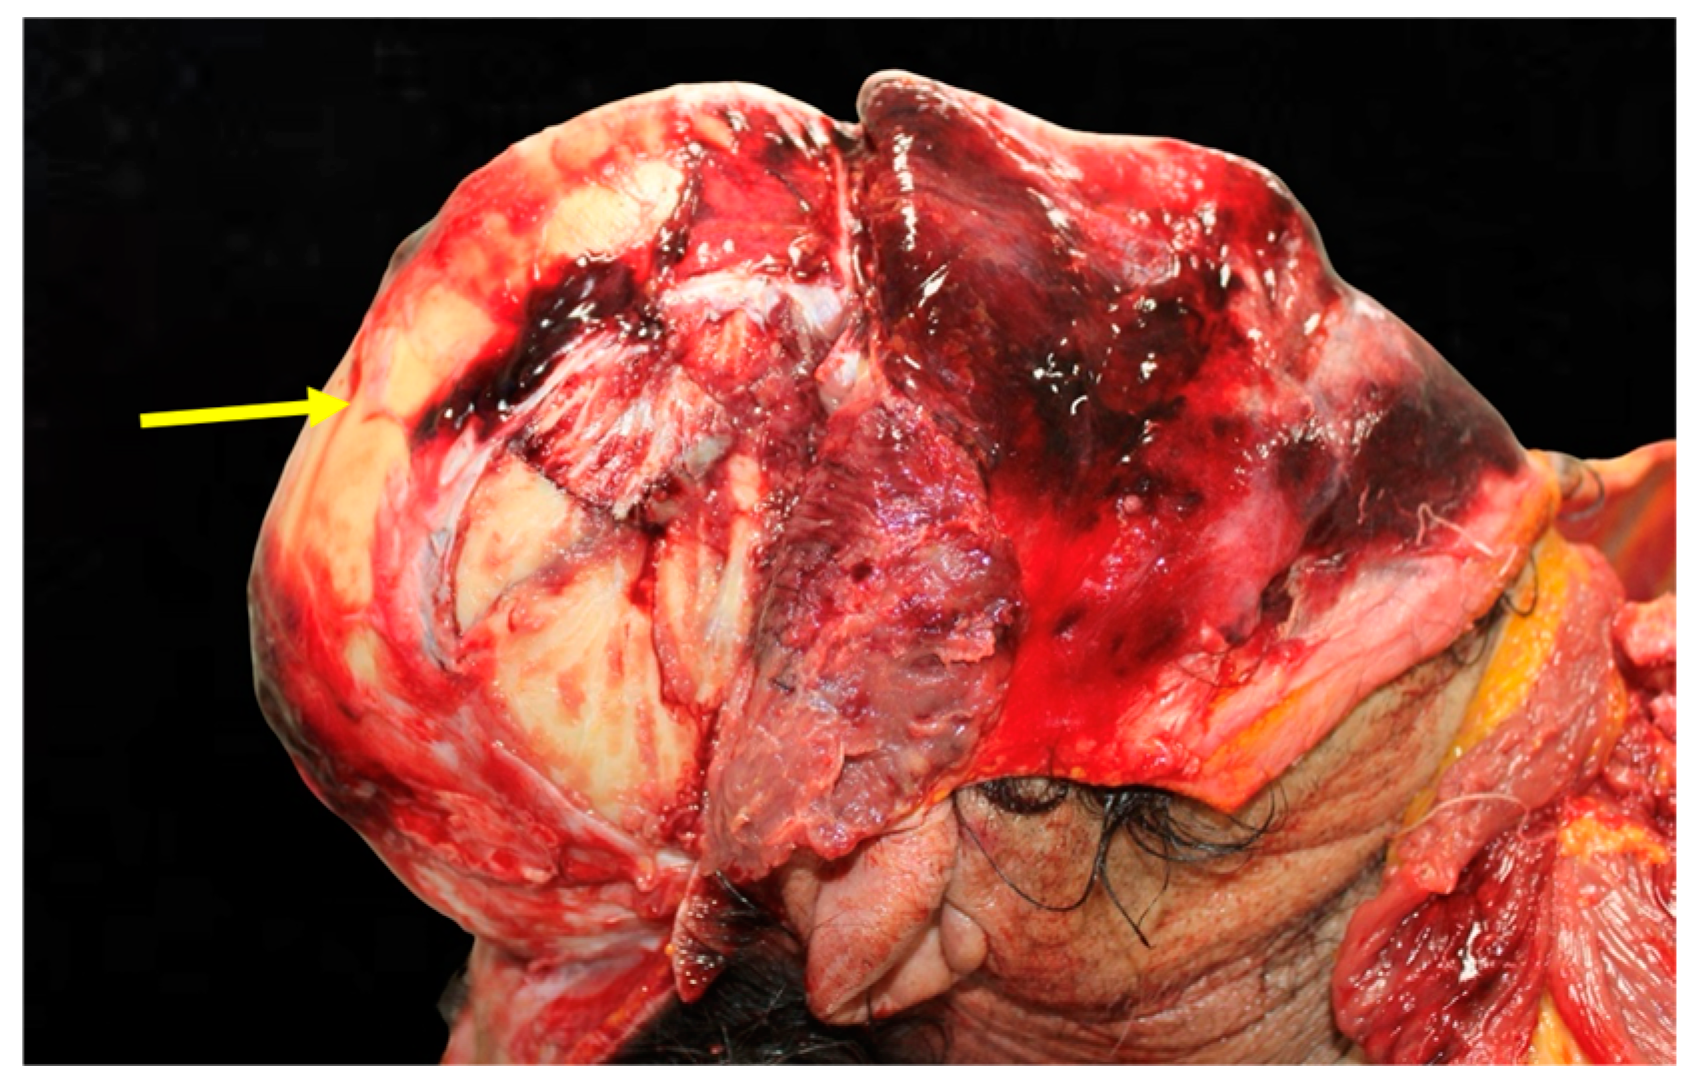

Figure 3. Trauma of the left parietotemporal region. The illustration shows localized contusions and fractures in the left parietotemporal region, correlating with lateral impacts.